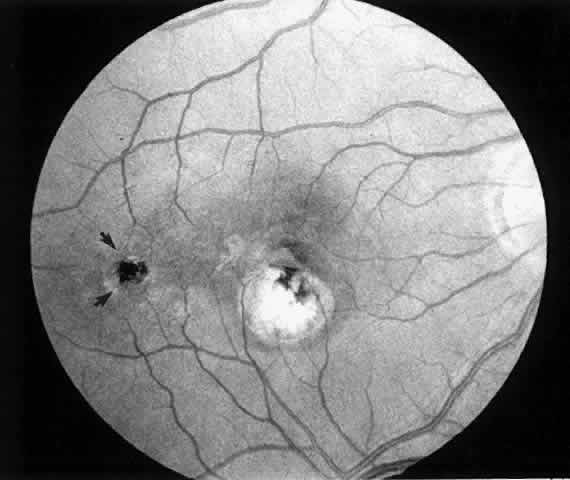

4. A 71-year-old patient with ARMD developed a recurrent choroidal neovascular membrane extending into the fovea with a preoperative vision of 20/320 (6/96) (Fig. 13). He had only marginal visual improvement after surgery (20/200 [6/60]) owing to a subfoveal RPE defect, but the size of the scotoma decreased after resolution of subretinal fluid (Fig. 14).

Fig. 13. Preoperative fluorescein angiogram (A) and Amsler grid (B) of a 71-year-old patient with age-related macular degeneration (case 4).

Fig. 14. Postoperative fundus photograph (A) and Amsler grid (B) (case 4). Central retinal pigment epithelial defect accounts for minimal visual improvement. Significant improvement is noted on Amsler grid.